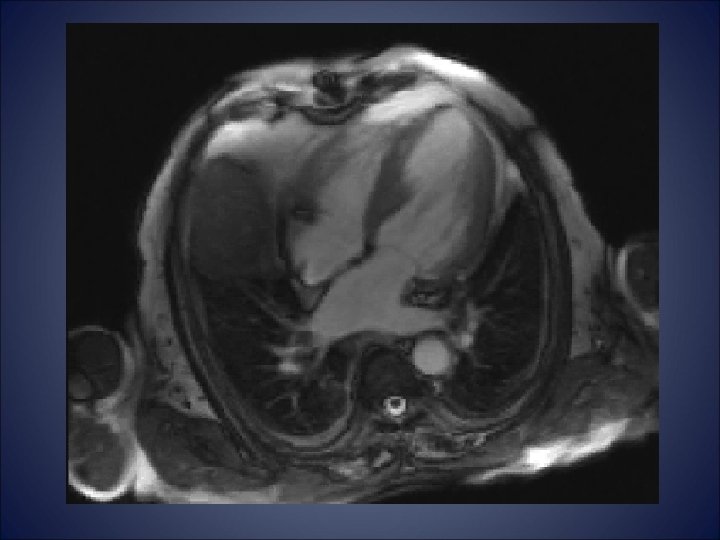

Cardiac MRI • The myocardium is thinned at the apical level with a diffuse

Cardiac MRI • The myocardium is thinned at the apical level with a diffuse delayed enhancement and moderately dyskinetic movement during the ventricular contraction • Fibrotic and non-viable tissue